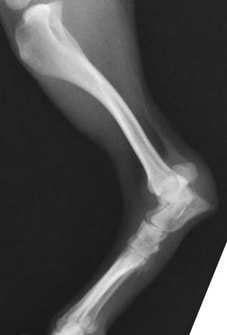

後肢の骨折:脛骨腓骨骨折

![]() 骨折時 |

![]() 手術後 |